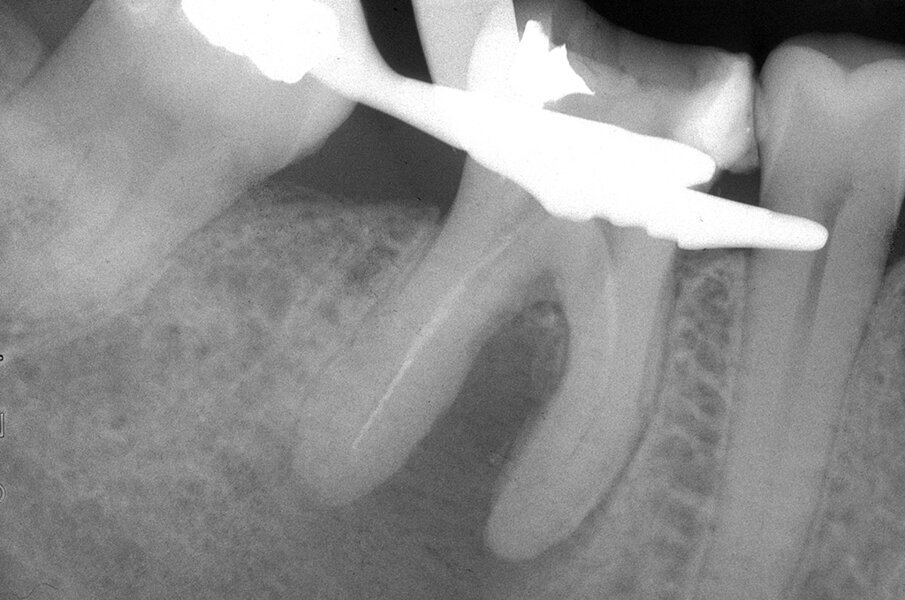

Queste perforazioni possono avvenire nel corso della strumentazione di canali curvi, per l’esecuzione del cosiddetto “trasporto esterno” del forame apicale. Una volta eseguita la perforazione, se l’operatore riesce a ritrovare e preparare il canale originale (con l’utilizzo di strumenti sottili e precurvati, molta irrigazione e soprattutto molta pazienza), il danno provocato dalla perforazione sarà minimo in quanto, soprattutto se la perforazione è piccola, si comporterà come un piccolo canale laterale che sarà facilmente otturato. Se invece il canale originale è rimasto intasato dai detriti di fango dentinale e gli strumenti ogni volta ripercorrono il cammino della perforazione, in tale caso il canale deve essere otturato con le metodiche tradizionali e successivamente l’apice contenente la porzione non trattata del canale radicolare deve essere rimosso per via chirurgica, soprattutto se stiamo trattando un dente necrotico o se siamo di fronte ad un ritrattamento (Figg. 1a-1e).